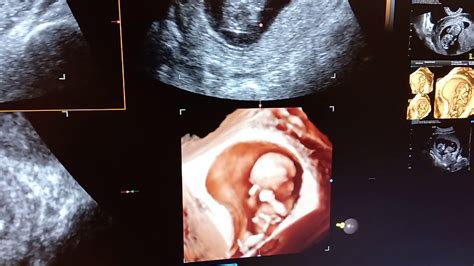

Diagnosticul unei sarcini fără embrion implică mai multe etape esențiale: anamneza și examenul clinic, testul de sarcină și ecografia. Prima etapă, anamneza și examenul clinic, presupune o discuție detaliată între medicul ginecolog și pacientă despre simptomele prezente și o examinare fizică a aparatului reproducător. Acestea oferă informații de bază despre starea generală de sănătate și istoricul medical al pacientei. Testul de sarcină este următorul pas și se realizează prin măsurarea nivelurilor de hCG (gonadotropina corionică umană) din urină sau sânge. Nivelul de hCG crește rapid la începutul sarcinii, atingând un vârf între săptămânile opt și zece. Se pot efectua mai multe măsurători pe parcursul câtorva zile pentru a monitoriza evoluția nivelurilor de hCG. Ecografia este o investigație foarte importantă și se poate efectua transabdominal sau transvaginal. Pentru un diagnostic precis, se preferă ecografia transvaginală, efectuată cu ajutorul unei sonde speciale. Sarcina anembrionară se diagnostichează în primul trimestru, între săptămânile șapte și nouă, când, în absența unui embrion vizibil, sacul gestațional are un diametru mediu de cel puțin 25 mm.